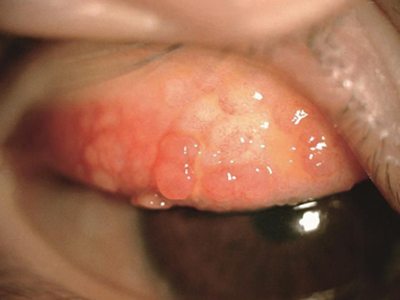

特应性角结膜炎眼皮里面有疙瘩图

特应性角结膜炎会导致患者眼皮内有乳头状的赘生物,即密集分布的圆形小疙瘩,质地较软,大小中等,患者会同时伴有上皮下纤维化的症状。